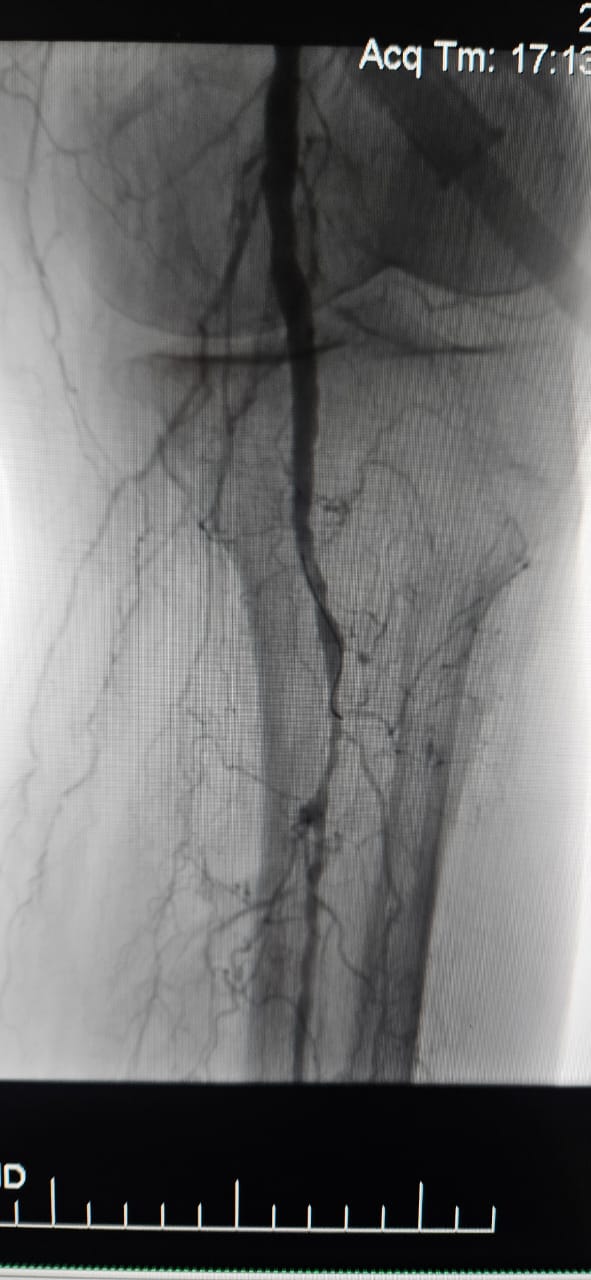

Nous sommes heureux de partager un cas réussi dans un hôpital de Batumi, en Géorgie, où une patiente de 78 ans atteinte d'ischémie critique des membres (ILC) causée par une occlusion totale chronique de l'artère du membre inférieur a montré une amélioration clinique remarquable après un traitement avec le système de cathéter de dilatation à ballonnet ThorCrack Peripheral IVL.

Ce cas souligne la valeur clinique de la lithotripsie intravasculaire (IVL) dans le traitement des cas CLI complexes avec une occlusion chronique à long segment-en particulier chez les patients présentant une calcification lourde, où les ballons traditionnels ou les dispositifs d'athérectomie peuvent avoir une efficacité limitée.

Nous sommes fiers de voir ThorCrack IVL permettre aux médecins du monde entier de surmonter les lésions calcifiées, de restaurer la perfusion et d'améliorer les résultats pour les patients atteints d'une maladie artérielle périphérique complexe.